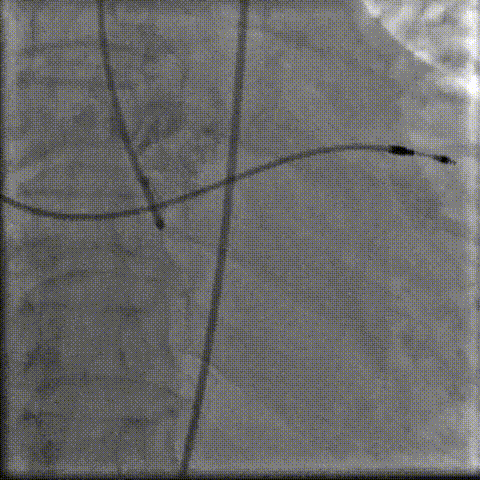

3.输送系统过弓

8.gif